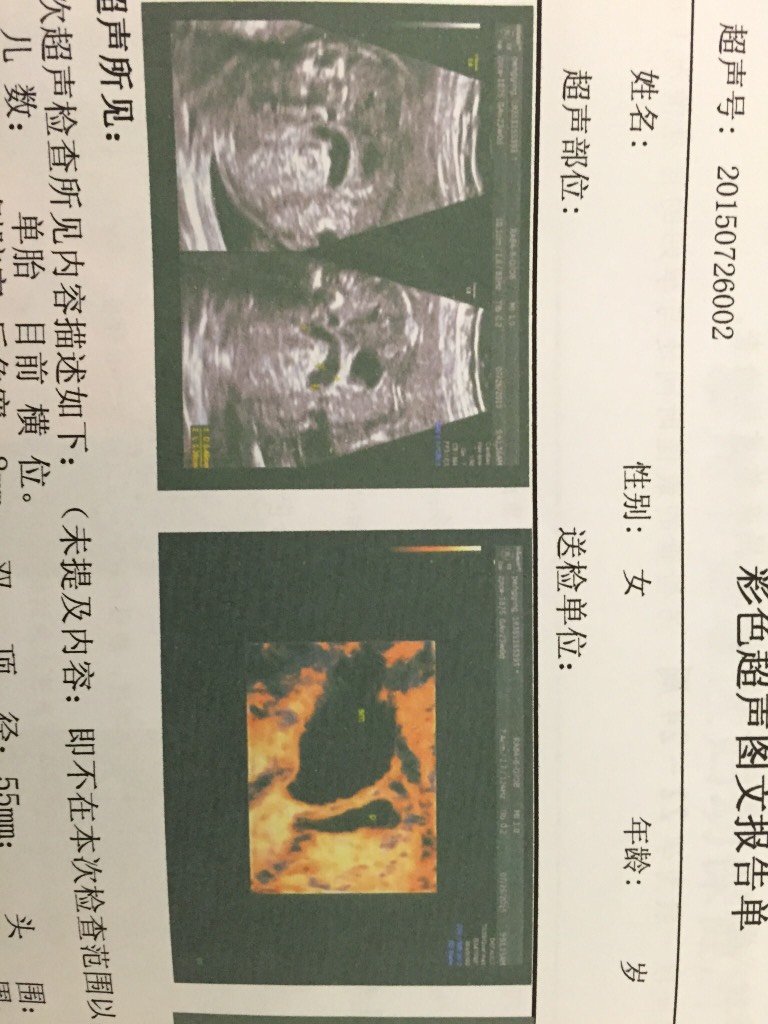

孕22周加6天,今天去做四维彩超,医生说胎儿胃泡旁有一腊肠样28mm*5mm大小无回声的不明结构 孕22周加6天,今天去做四维彩超,医生说胎儿胃泡旁有一腊肠样28mm*5mm大小无回声的不明结构,与胃不相连,请问是不是消化道畸形啊?要怎么办? 点击展开 彭小颖 2015-07-26 13:52 为您推荐: 其他回答 医生怎么说? 菜媛子@ 2015-07-27 13:58 看不懂,拿了結果給醫生看啊 张小严 2015-07-27 10:56 定期,检查。, 女人一世 2015-07-26 23:55 不会看。。。 A凯里宝妈 2015-07-26 22:52 再等等做个四维吧 我的年少时 2015-07-26 20:44 加载更多 相关问题 孕9周加6,B超显示有积液28*8,怎么办,其他都好,33×15的胚胎回声,胎心搏动 有医生在吗?请帮我看看这种情况胎盘长上去的机率是多少?我现在是孕12周加1天 到今天孕7周加6天了,应该去医院做哪些检查?前两周做过一次B超,B超表明尚未发现胎芽胎心,医生让我